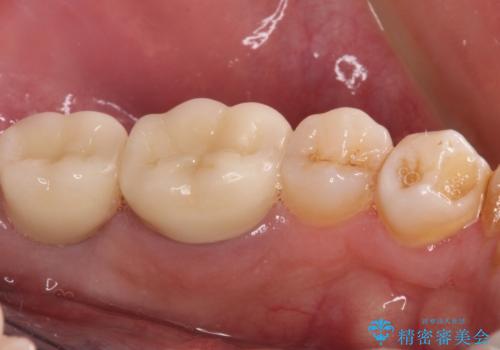

抜歯が必要な奥歯 ストローマン・インプラント補綴治療

- 近医にて奥歯の抜歯が必要と言われたとのことで来院された患者様です。

診査の結果、歯が破折しており、抜歯が必要な状態でした。

最後方歯であるため、入れ歯かインプラントかどちらかの補綴治療を行うこととなりますが、ご希望によりインプラント補綴治療を行うこととしました。

インプラントにはストローマン社のSLActiveを使用し、埋入から補綴までおよそ3か月と、短期間で治療を進めることができました。